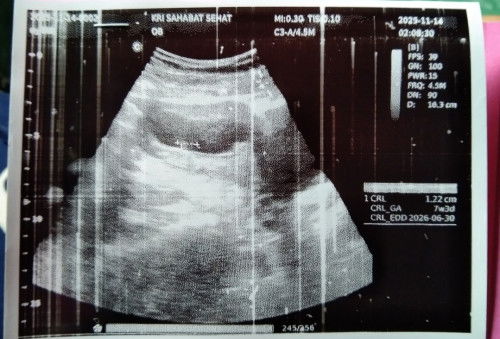

Baca lagiaku jg gtu Bun tespek garis 1 tp USG udah 7 week udah ada CRL nya janinnya ukuran 1,22cm